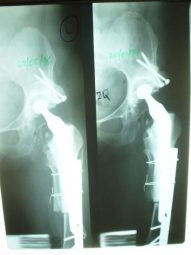

Revisión de prótesis con injerto óseo masivo

Envíado por Dr. Ricardo Antonio Gómez G.